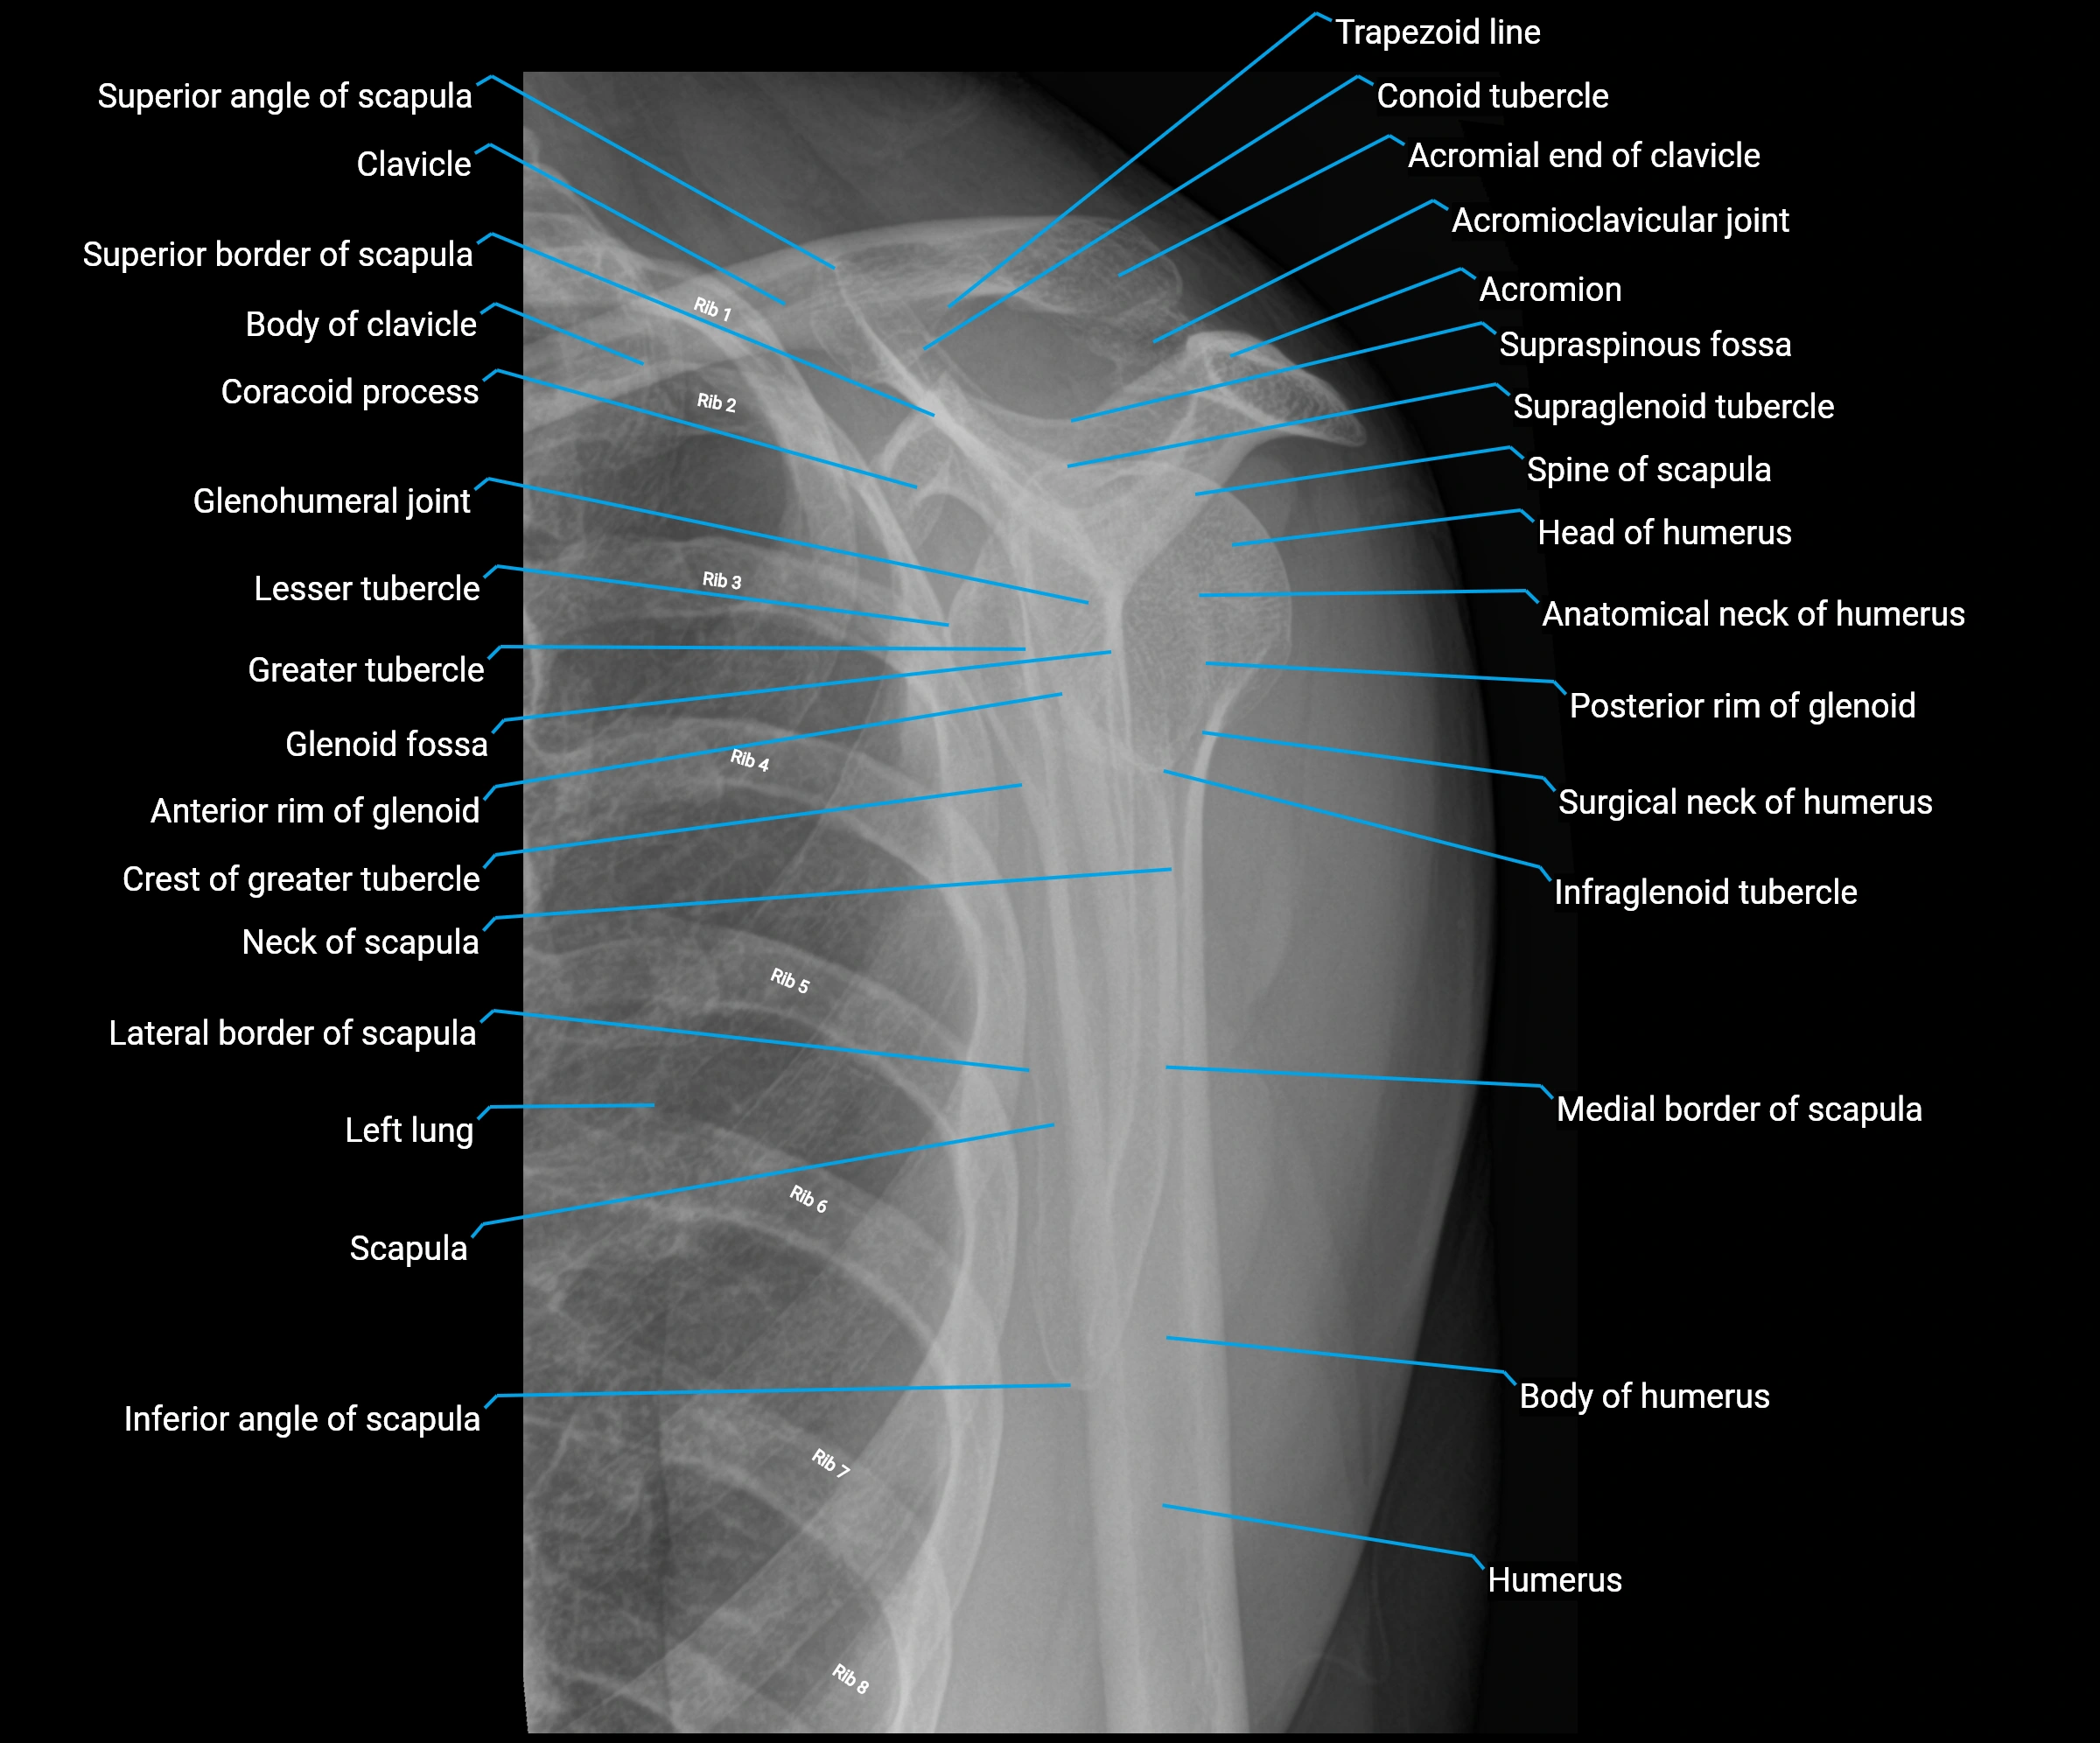

The acromial end of the clavicle is the flattened lateral extremity of the clavicle that articulates with the acromion of the scapula to form the acromioclavicular (AC) joint. Unlike the sternal end, the acromial end is broad and compressed. Its articular surface is oval, directed downward and medially, and covered with fibrocartilage.

The AC joint is stabilized by the acromioclavicular ligaments (superior and inferior) and reinforced by the coracoclavicular ligaments (conoid and trapezoid), which prevent vertical displacement. Small intra-articular fibrocartilaginous discs may be present.

This region is highly mobile, allowing scapular rotation, gliding, and elevation, which are essential for full shoulder motion. It is clinically significant as a frequent site of degeneration, separation injuries, fractures, and osteoarthritis.